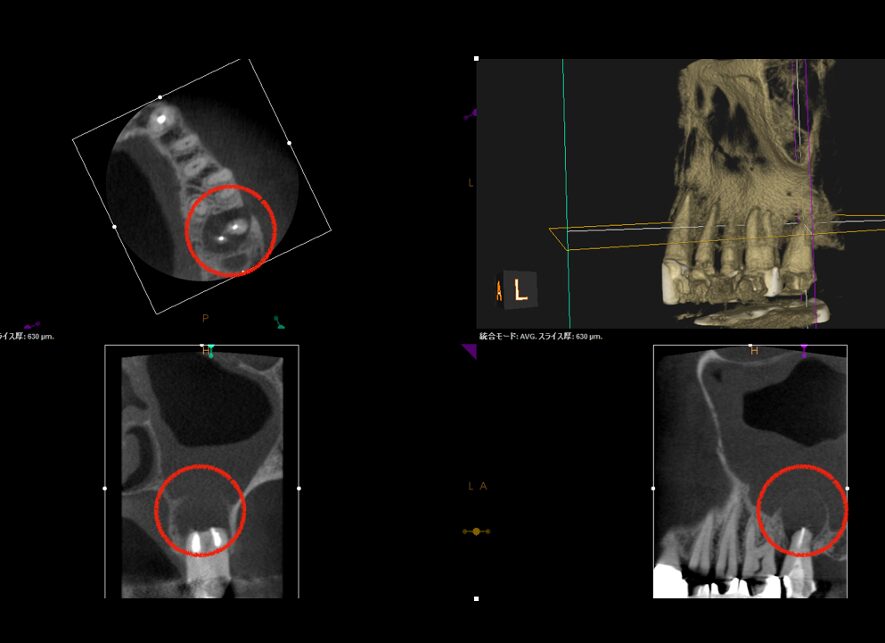

本症例の患者様は、左上7番(第2大臼歯)の歯ぐきから膿が出ており、来院されました。口腔内を確認すると根尖性歯周炎(※1)が原因で、左上7番根尖部(歯の根の先)に、瘻孔(フィステル・サイナストラクト ※2)が確認できました。CTにて膿が出ている箇所(写真の赤矢印)を確認すると、左上7番の根尖部に大きく広がっている病変(写真の赤丸)へ繋がっていることが分かりました。

当院で精密根管治療を施しましたが、瘻孔(フィステル・サイナストラクト)を消失させることが難しく、追加処置として歯根端切除術(今回は意図的再植術)を行いました。また、術前に撮影したCT画像より、根尖性歯周炎が原因と考えられる上顎洞炎(蓄膿症/ちくのうしょう)の併発も確認できました。